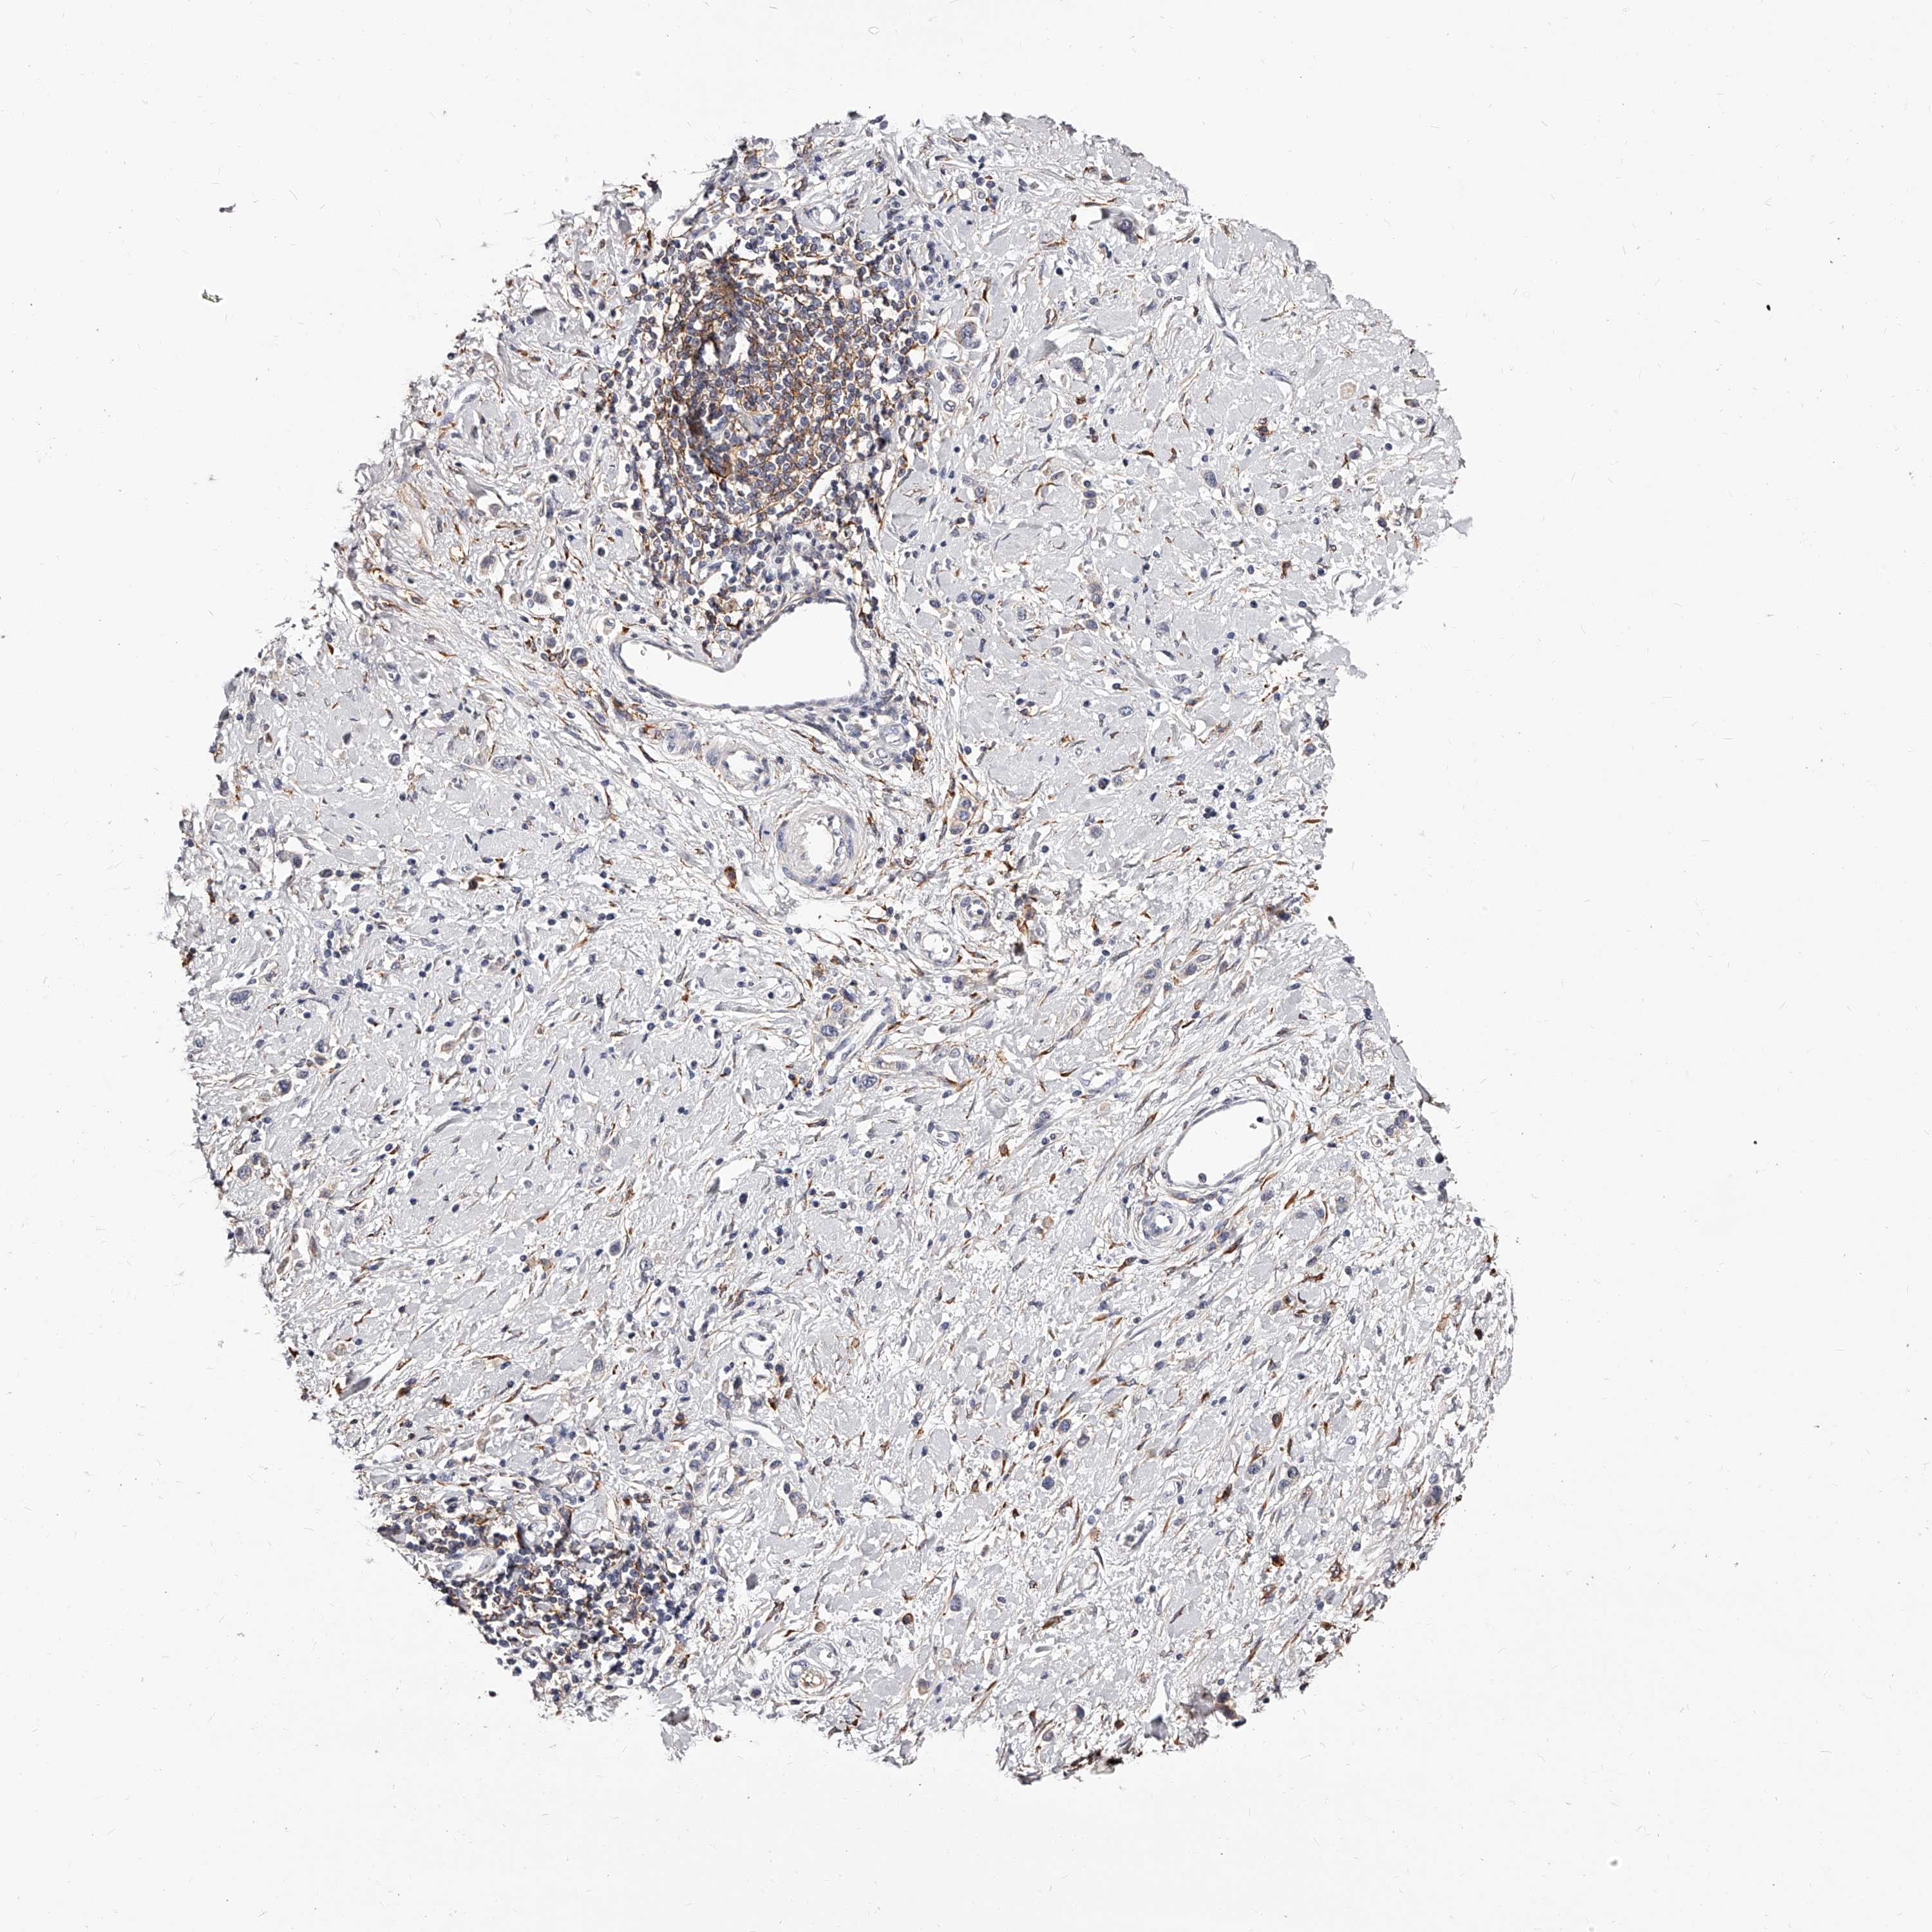

STOMACH CANCER - Protein expressioni

A mouse-over function shows sample information and annotation data. Click on an image to view it in a full screen mode. Samples can be filtered based on level of antibody staining by selecting one or several of the following categories: high, medium, low and not detected. The assay and annotation is described here.

Note that samples used for immunohistochemistry by the Human Protein Atlas do not correspond to samples in the TCGA dataset.

Antibody stainingi

Antibody staining in the annotated cell types in the current human tissue is reported as not detected, low, medium, or high, based on conventional immunohistochemistry profiling in selected tissues. This score is based on the combination of the staining intensity and fraction of stained cells.

Each image is clickable and will lead to virtual microscopy that enables deeper exploration of all samples and also displays staining intensity scores, fraction scores and subcellular localization as well as patient and tissue information for each sample.

Antibody HPA028900

Antibody CAB002508

Staining

High

Medium

Low

Not detected

Intensity

Strong

Moderate

Weak

Negative

Quantity

>75%

75%-25%

<25%

None

Location

Nuclear

Cytoplasmic/membranous

Cytoplasmic/membranous,nuclear

Adenocarcinoma, NOS